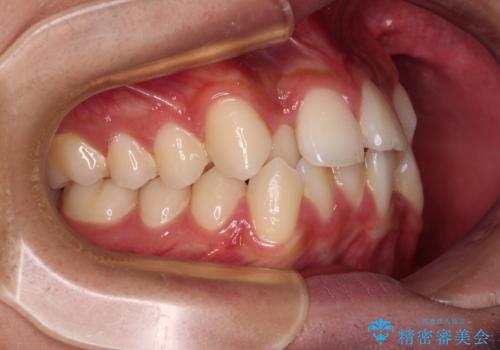

- 八重歯と口元の閉じにくさを気にして来院された患者様です。

非抜歯矯正で歯列を整えると、治療後に口元が今よりも突出する可能性が高かったため、上下左右の第一小臼歯4本を抜歯し、ワイヤー装置にて矯正治療を行うこととしました。